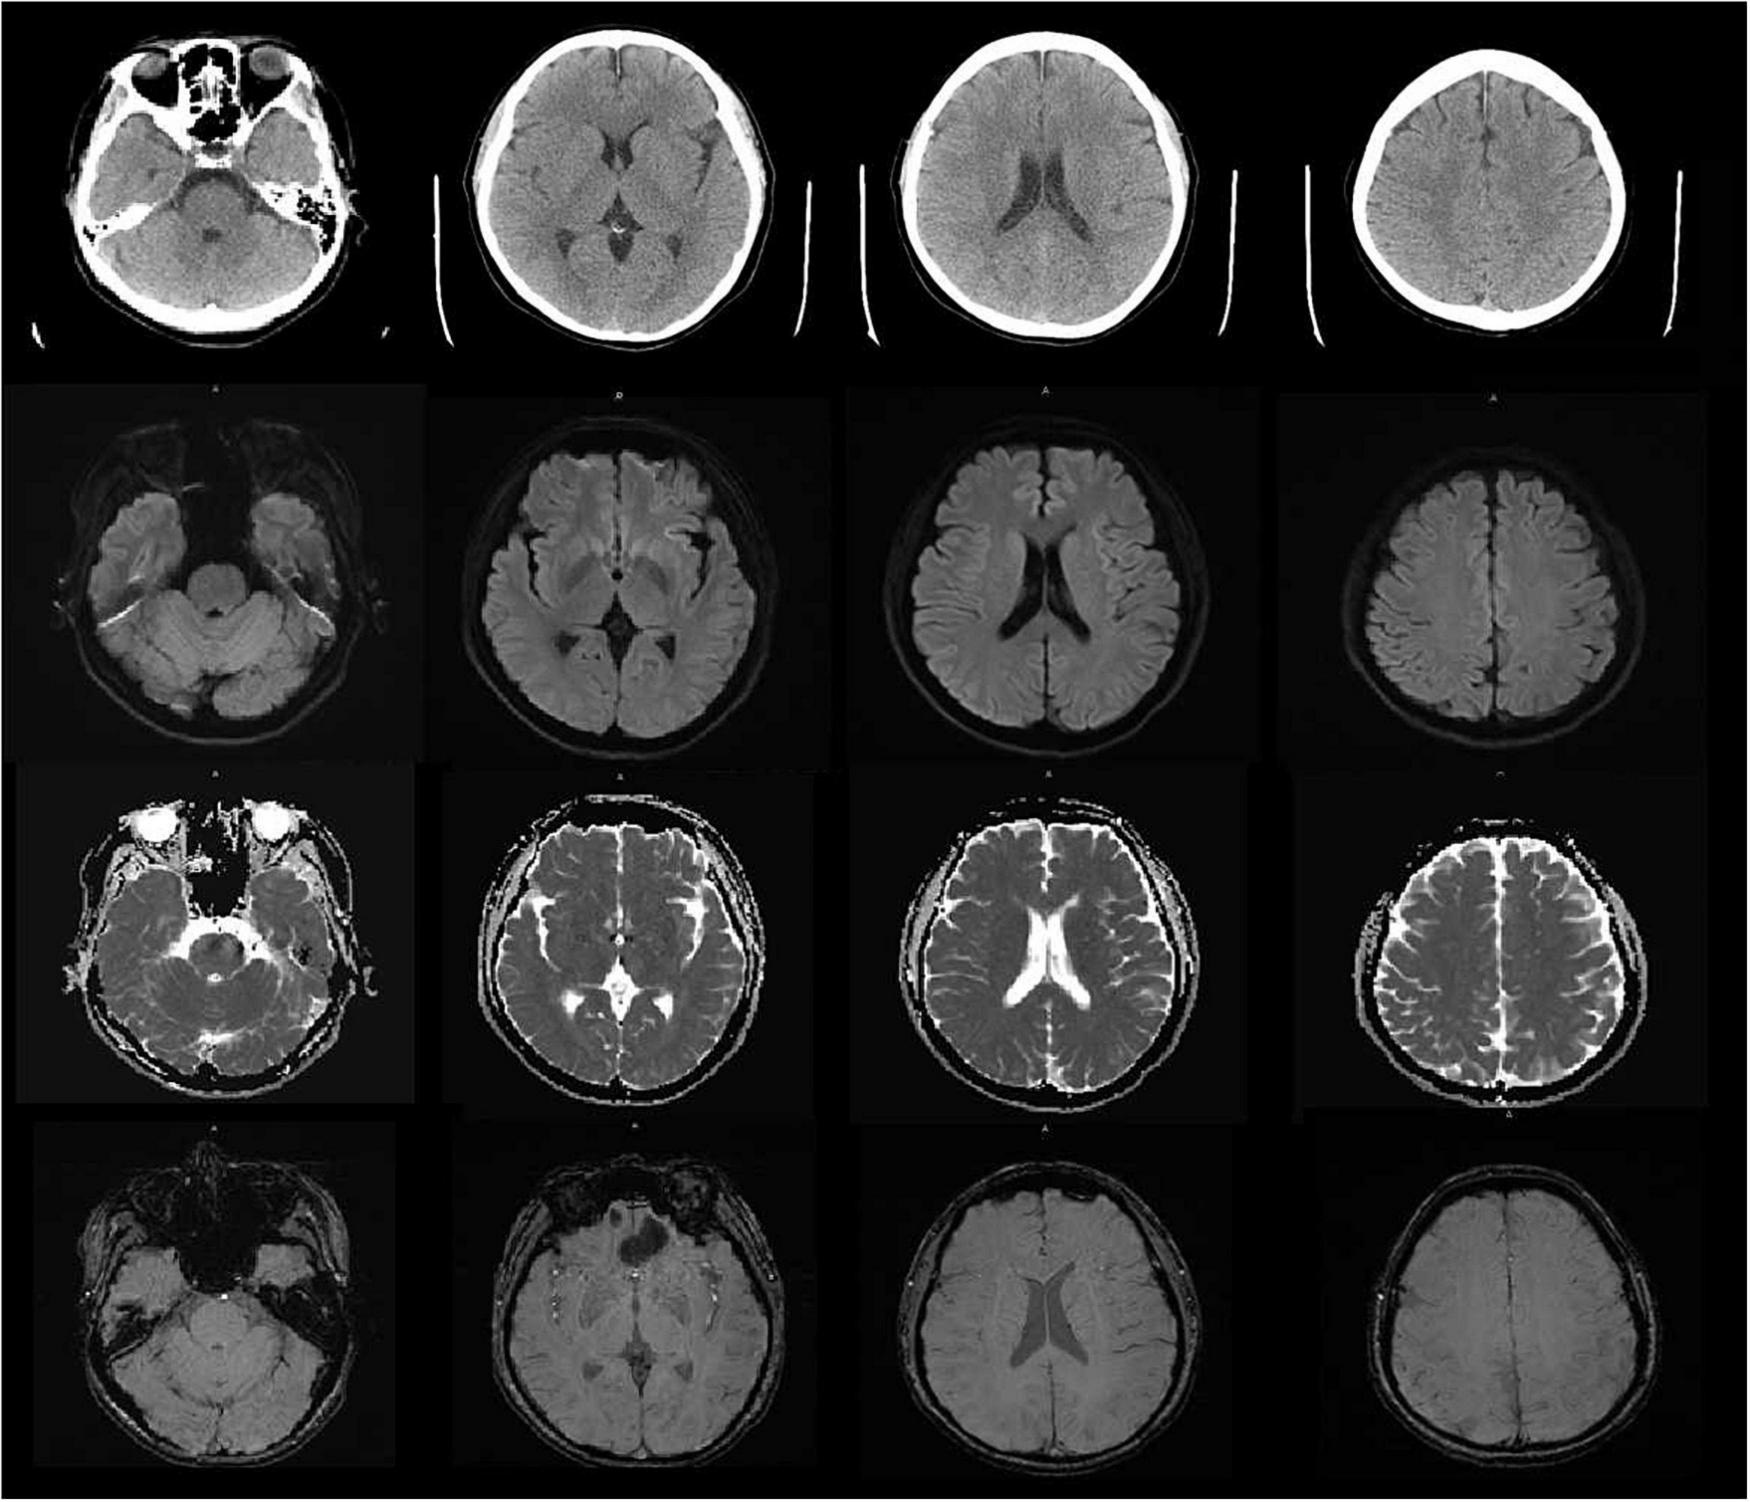

Vital signs were monitored within 24 h after admission; the patient got external auditory canal bleeding 3 h after thrombolysis. The further investigation and inquiry on her medical history showed a history of ear trauma 1 week before. Bleeding was stopped via external auditory canal tamponage. The cranial MRI and systemic vascular examination were arranged to find the cause of stroke, no abnormal signal was found in T1-weighted imaging, T1WI (T1), T2-weighted imaging, T2WI (T2), and diffusion-weighted imaging (DWI), and there was no microhemorrhage-related signal in susceptibility weighted imaging (SWI) (Figure 2). In the magnetic resonance angiography (MRA) measurement, intracranial vessels were indicated normal and bilateral embryonic posterior cerebral arteries were observed. Carotid ultrasound showed bilateral carotid intima thickening with plaque formation and plaque was found in the right subclavian artery. Arteriovenous ultrasound of lower extremity showed normal. Transcranial Doppler showed a rapid increase in the flow rate of the left middle cerebral artery, and 5–6 microembolic could be found in foaming experiment, supporting a direct pathway from pulmonary circulation to the systemic circulation (RLS). Cardiac systemic examination was completed: 24-h Holter showed sinus bradycardia, short atrial tachycardia, and atrial premature beats (some of which were not transmitted). Widening ascending aorta was shown on echocardiography. Thrombus was not found in bilateral atrium and left auricle in transesophageal echocardiography, also no septal shunt beam was observed in the atrial septal fossa ovale. From the data that were collected from the other hospital, left atrium was slightly larger and the middle branch of the right pulmonary vein was mutated on the CT angiography (CTA) of the left atria and pulmonary veins on 26th September (Figure 3). Diagnosis of transient ischemic attack, cardiogenic cerebral embolism, paroxysmal atrial fibrillation, pulmonary arteriovenous fistula, hypertension with Grade 2, and hyperlipidemia were observed after admission. She was suggested to restart the anticoagulant treatment deal to the CHA2DS2-VAS score was 4 and HAS-BLED score was 2. The pulmonary artery digital subtraction angiography (DSA) was also suggested after patients were discharged.

FIGURE 2

The cranial MRI showed no abnormal signal was found in T1-weighted imaging, T1WI (TI), T2-weighted imaging, T2WI (T2), diffusion-weighted imaging (DWI) and susceptibility weighted imaging (SWI).